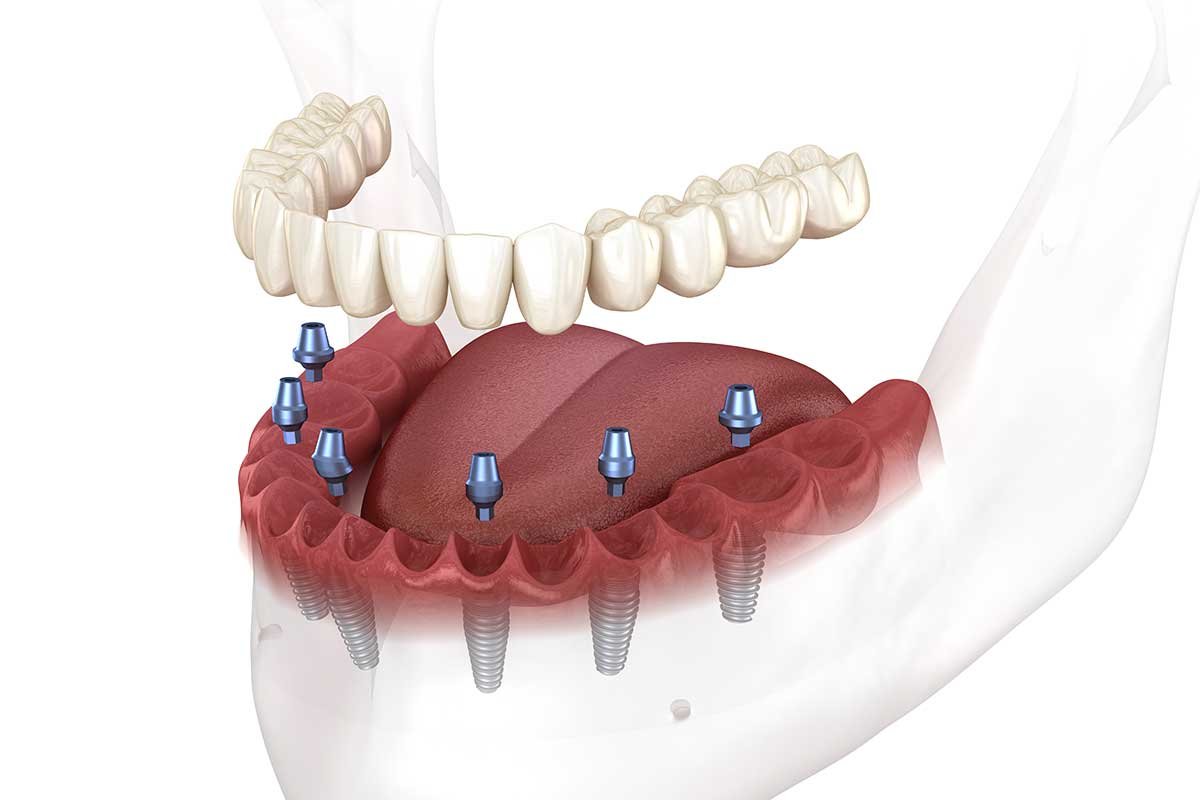

¿Son necesarios antes de colocar implantes dentales?

Si usted ha tenido una endodoncia y se prepara para un implante dental, tal vez se le recomiende profilaxis antibiótica. Esta decisión depende de su historial médico, salud general y posibles infecciones previas.